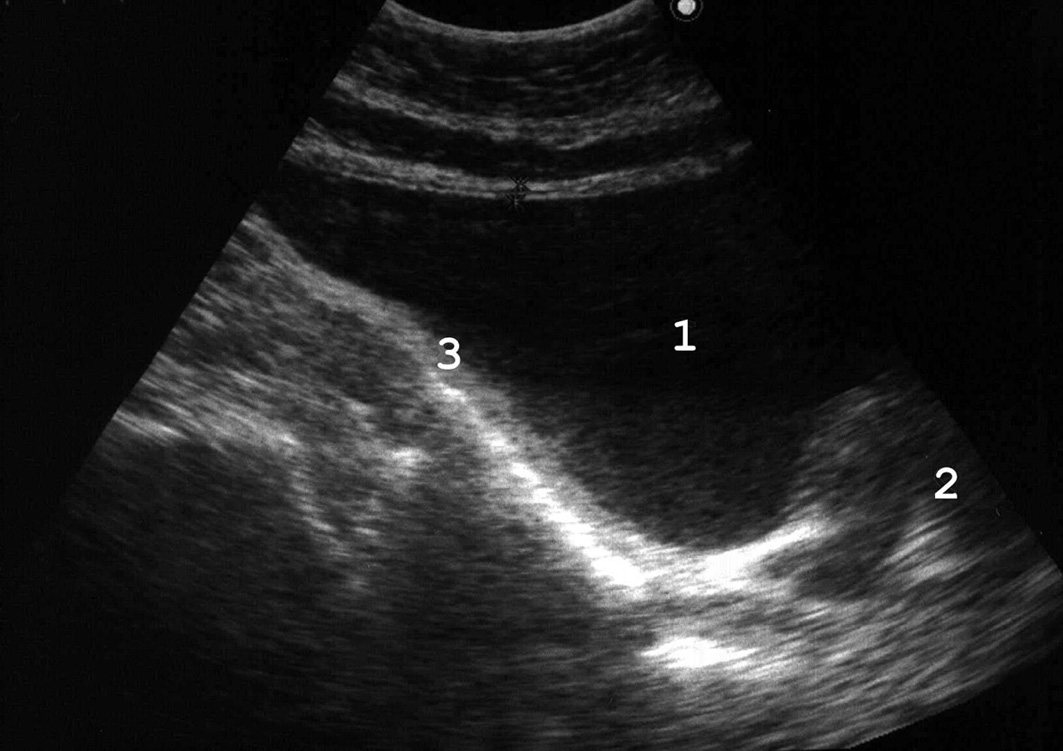

Рис. 17. Мочевой пузырь при цистите, пиурии. Вязкий гной образует причудливые фигуры на дне пузыря, при изменении положения тела он медленно перемещается, почти не меняя формы. (Поперечное сканирование, А − в положении пациента на спине, Б − на левом боку. Конвексный датчик 5 МГц, “Logiq-500”).